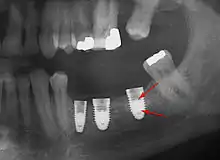

Long-term failures are due to either loss of bone around the tooth and/or gingiva due to peri-implantitis or a mechanical failure of the implant. Because there is no dental enamel on an implant, it does not fail due to cavities like natural teeth. While large-scale, long-term studies are scarce, several systematic reviews estimate the long-term (five to ten years) survival of dental implants at 93–98 percent depending on their clinical use.[1][2][3] During initial development of implant retained teeth, all crowns were attached to the teeth with screws, but more recent advancements have allowed placement of crowns on the abutments with dental cement (akin to placing a crown on a tooth). This has created the potential for cement, that escapes from under the crown during cementation to get caught in the gingiva and create a peri-implantitis (see picture below). While the complication can occur, there does not appear to be any additional peri-implantitis in cement-retained crowns compared to screw-retained crowns overall.[64] In compound implants (two stage implants), between the actual implant and the superstructure (abutment) are gaps and cavities into which bacteria can penetrate from the oral cavity. Later these bacteria will return into the adjacent tissue and can cause periimplantitis.